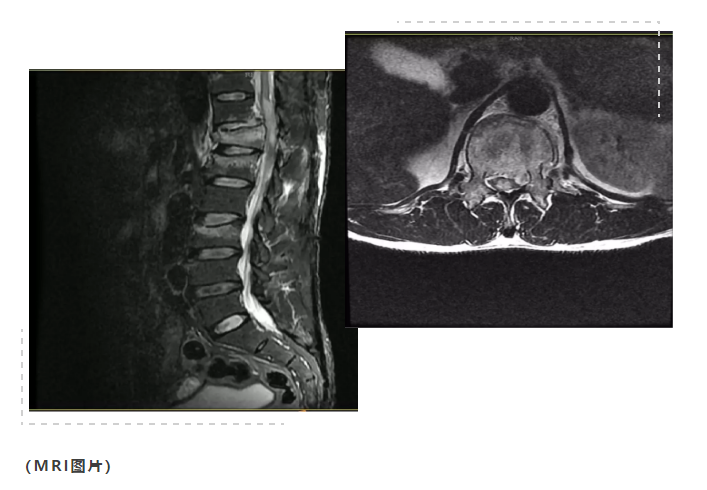

本院腰椎MRI示:

胸12压缩明显,腰1、3椎体上缘轻度压缩骨折,胸12平面脊髓片状高信号。